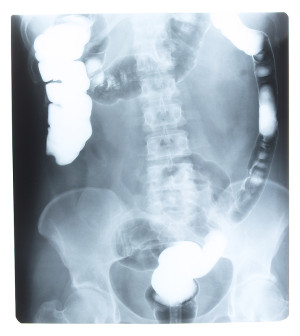

(HealthDay News) — Inflammatory bowel disease (IBD) includes a number of disorders that lead to an inflammation of the intestines.

- Gallstones or kidney stones.